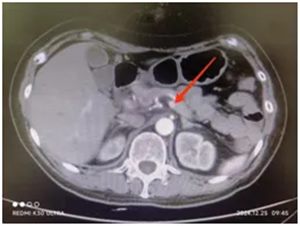

根据罗女士典型的症状及仔细阅读随身带来的影像资料,陈艳军主任初步判断胰岛素瘤的可能性大,并立即收治入院。入院后请内分泌科会诊,积极完善血糖、血胰岛素、C肽、COR、ACTH、胃泌素、儿茶酚胺等化验检查,先后排除了垂体、肾上腺、自身免疫等疾病所引起低血糖症的可能,进行上腹部增强CT及MRI检查,发现胰腺体尾部多发占位,根据化验检查资料可明确诊断,患者的低血糖是由胰岛素瘤引起的。

胰腺增强CT:胰尾影稍增粗,增强扫描动脉期见多发结节状明显强化影,较大者直径约1cm,考虑胰腺胰岛素瘤。